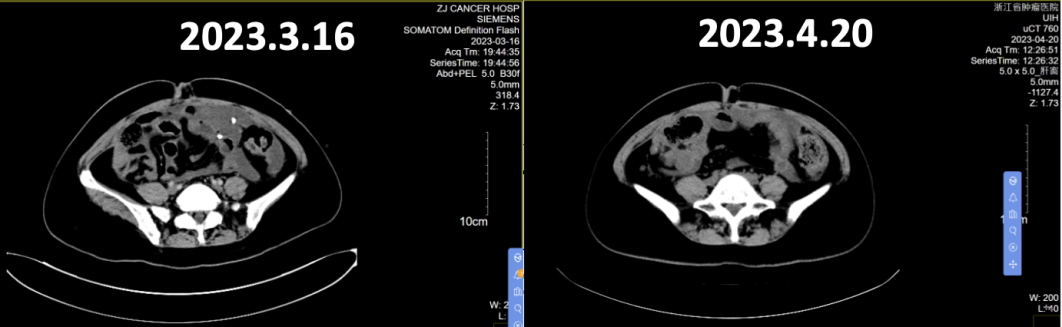

全腹CT(2023年3月16日):盆腔见囊实性灶,肝表面、大网膜及盆底腹膜多发结节灶,考虑转移,较前似饱满。腹盆腔积液,较前增多。右侧斜裂胸膜不均匀增厚,较前明显,转移考虑。右侧胸腔积液,较前增多。右侧心膈角增大淋巴结,较前缩小,考虑转移。疗效评价为疾病进展(PD)。

全腹CT:肝表面、腹膜、肠表面及盆腔系膜多发结节灶及增厚,考虑转移,部分较前稍缩小;腹盆腔积液,较前稍吸收。右侧斜裂胸膜不均匀增厚,较前缩小,转移考虑。右侧胸腔少量积液,较前明显吸收。双侧心膈角增大淋巴结,较前缩小,考虑转移。疗效评价为部分缓解(PR)。